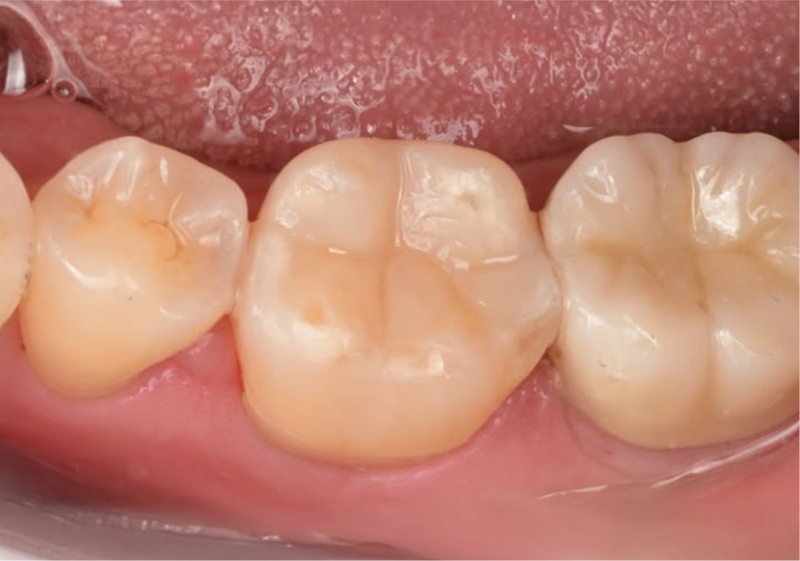

레진빌드업

자연치아를 위한 신중한 접근,

한 땀 한 땀 정성을 더하다.

치과의사의 손길로 빚어내는, 섬세한 치아 수복

레진빌드업은 치과의사가 구강 내에서

직접 치아의 형태를 세심하게 만들어나가는 수복 방식입니다.

자연치아의 구조를 모방(biomimetic) 하여

신중하게 접착하는 과정을 거치며,

본래 치아와 조화롭게 기능할 수 있도록 돕습니다.

레진빌드업, 이러한 가치를 담아 진료합니다

보존 중심 접근 │ 자연치아의 건강한 부분을 가능한 보존하는 것을 목표로 진료 계획을 세웁니다.책임감 있는 진료 │ 상담부터 마무리까지, 모든 과정을 치과의사가 직접 세심하게 진행합니다.정밀 접착 과정 │ 치아와 재료가 긴밀하게 결합될 수 있도록 세심한 접착 단계를 거칩니다.자연스러운 조화 │ 주변 치아와의 색상이나 형태 등 전체적인 조화를 고려하여 수복을 진행합니다.